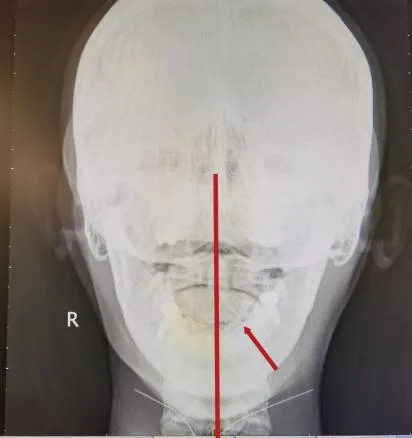

寰枢关节位于颈椎最上端,是连接头部和颈椎的关键部位。一旦发生错位或失稳,可能会压迫椎动脉,影响大脑供血,导致头晕、头痛、恶心等症状,严重时甚至引发体位性眩晕或跌倒。

1.精准定位:通过触诊和影像学检查,锁定错位椎体,精准定位治疗。